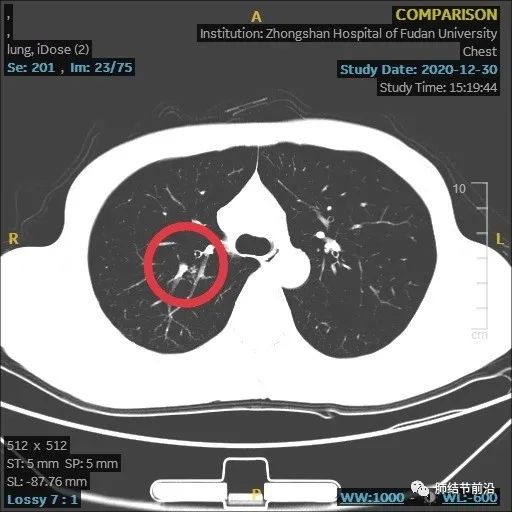

结节变大,形态变化,出现多中心微小结节堆积形态,而之前实性8mm结节却不见了。

虽然结节变大,但这个时候反而安心了,大的8mm实性结节消失,变成多中心微小结节。这样不符合肺癌的发展规律,考虑炎症性结节。因为恶性结节,只会实性成分扩大。

给予抗生素治疗,建议再3个月复查。